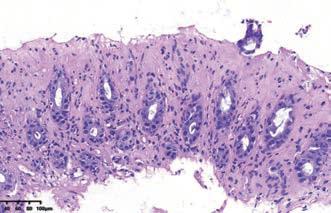

图解:炎症性肠病毒性/缺血黏膜损伤模式病理图(HE × 4 物镜)黏膜上半部隐窝萎缩,细胞变立方形,胞质黏液减少,黏膜固有层炎症细胞少,间质透明变,表面上皮脱落

这种粘膜损伤的模式是指肠粘膜上半部隐窝萎缩、细胞体积变小,呈立方状、胞质黏液减少。可见隐窝细胞凋亡增多、隐窝枯萎(crypt withering/withered crypts)等表现。这种病理改变,多见于缺血性肠病、药物性肠炎、病毒感染等。